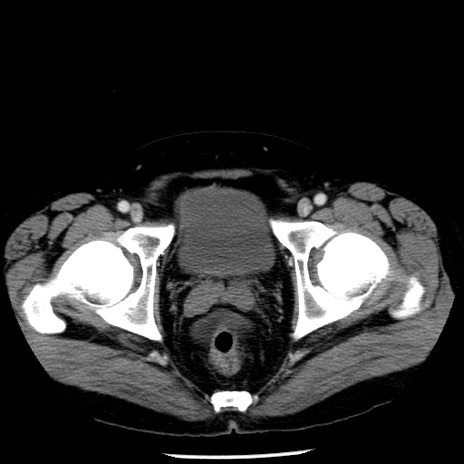

症例29(横断像)

【症例】40歳代男性

【現病歴】2日前から胃痛あり。徐々に周期的な激痛に変化した。本日になっても激痛があるため受診。

【身体所見】意識清明、BT 38-39℃台あり、腹部:膨満、やや硬、右下腹部に圧痛あり。

【データ】WBC 8500、CRP 23.26